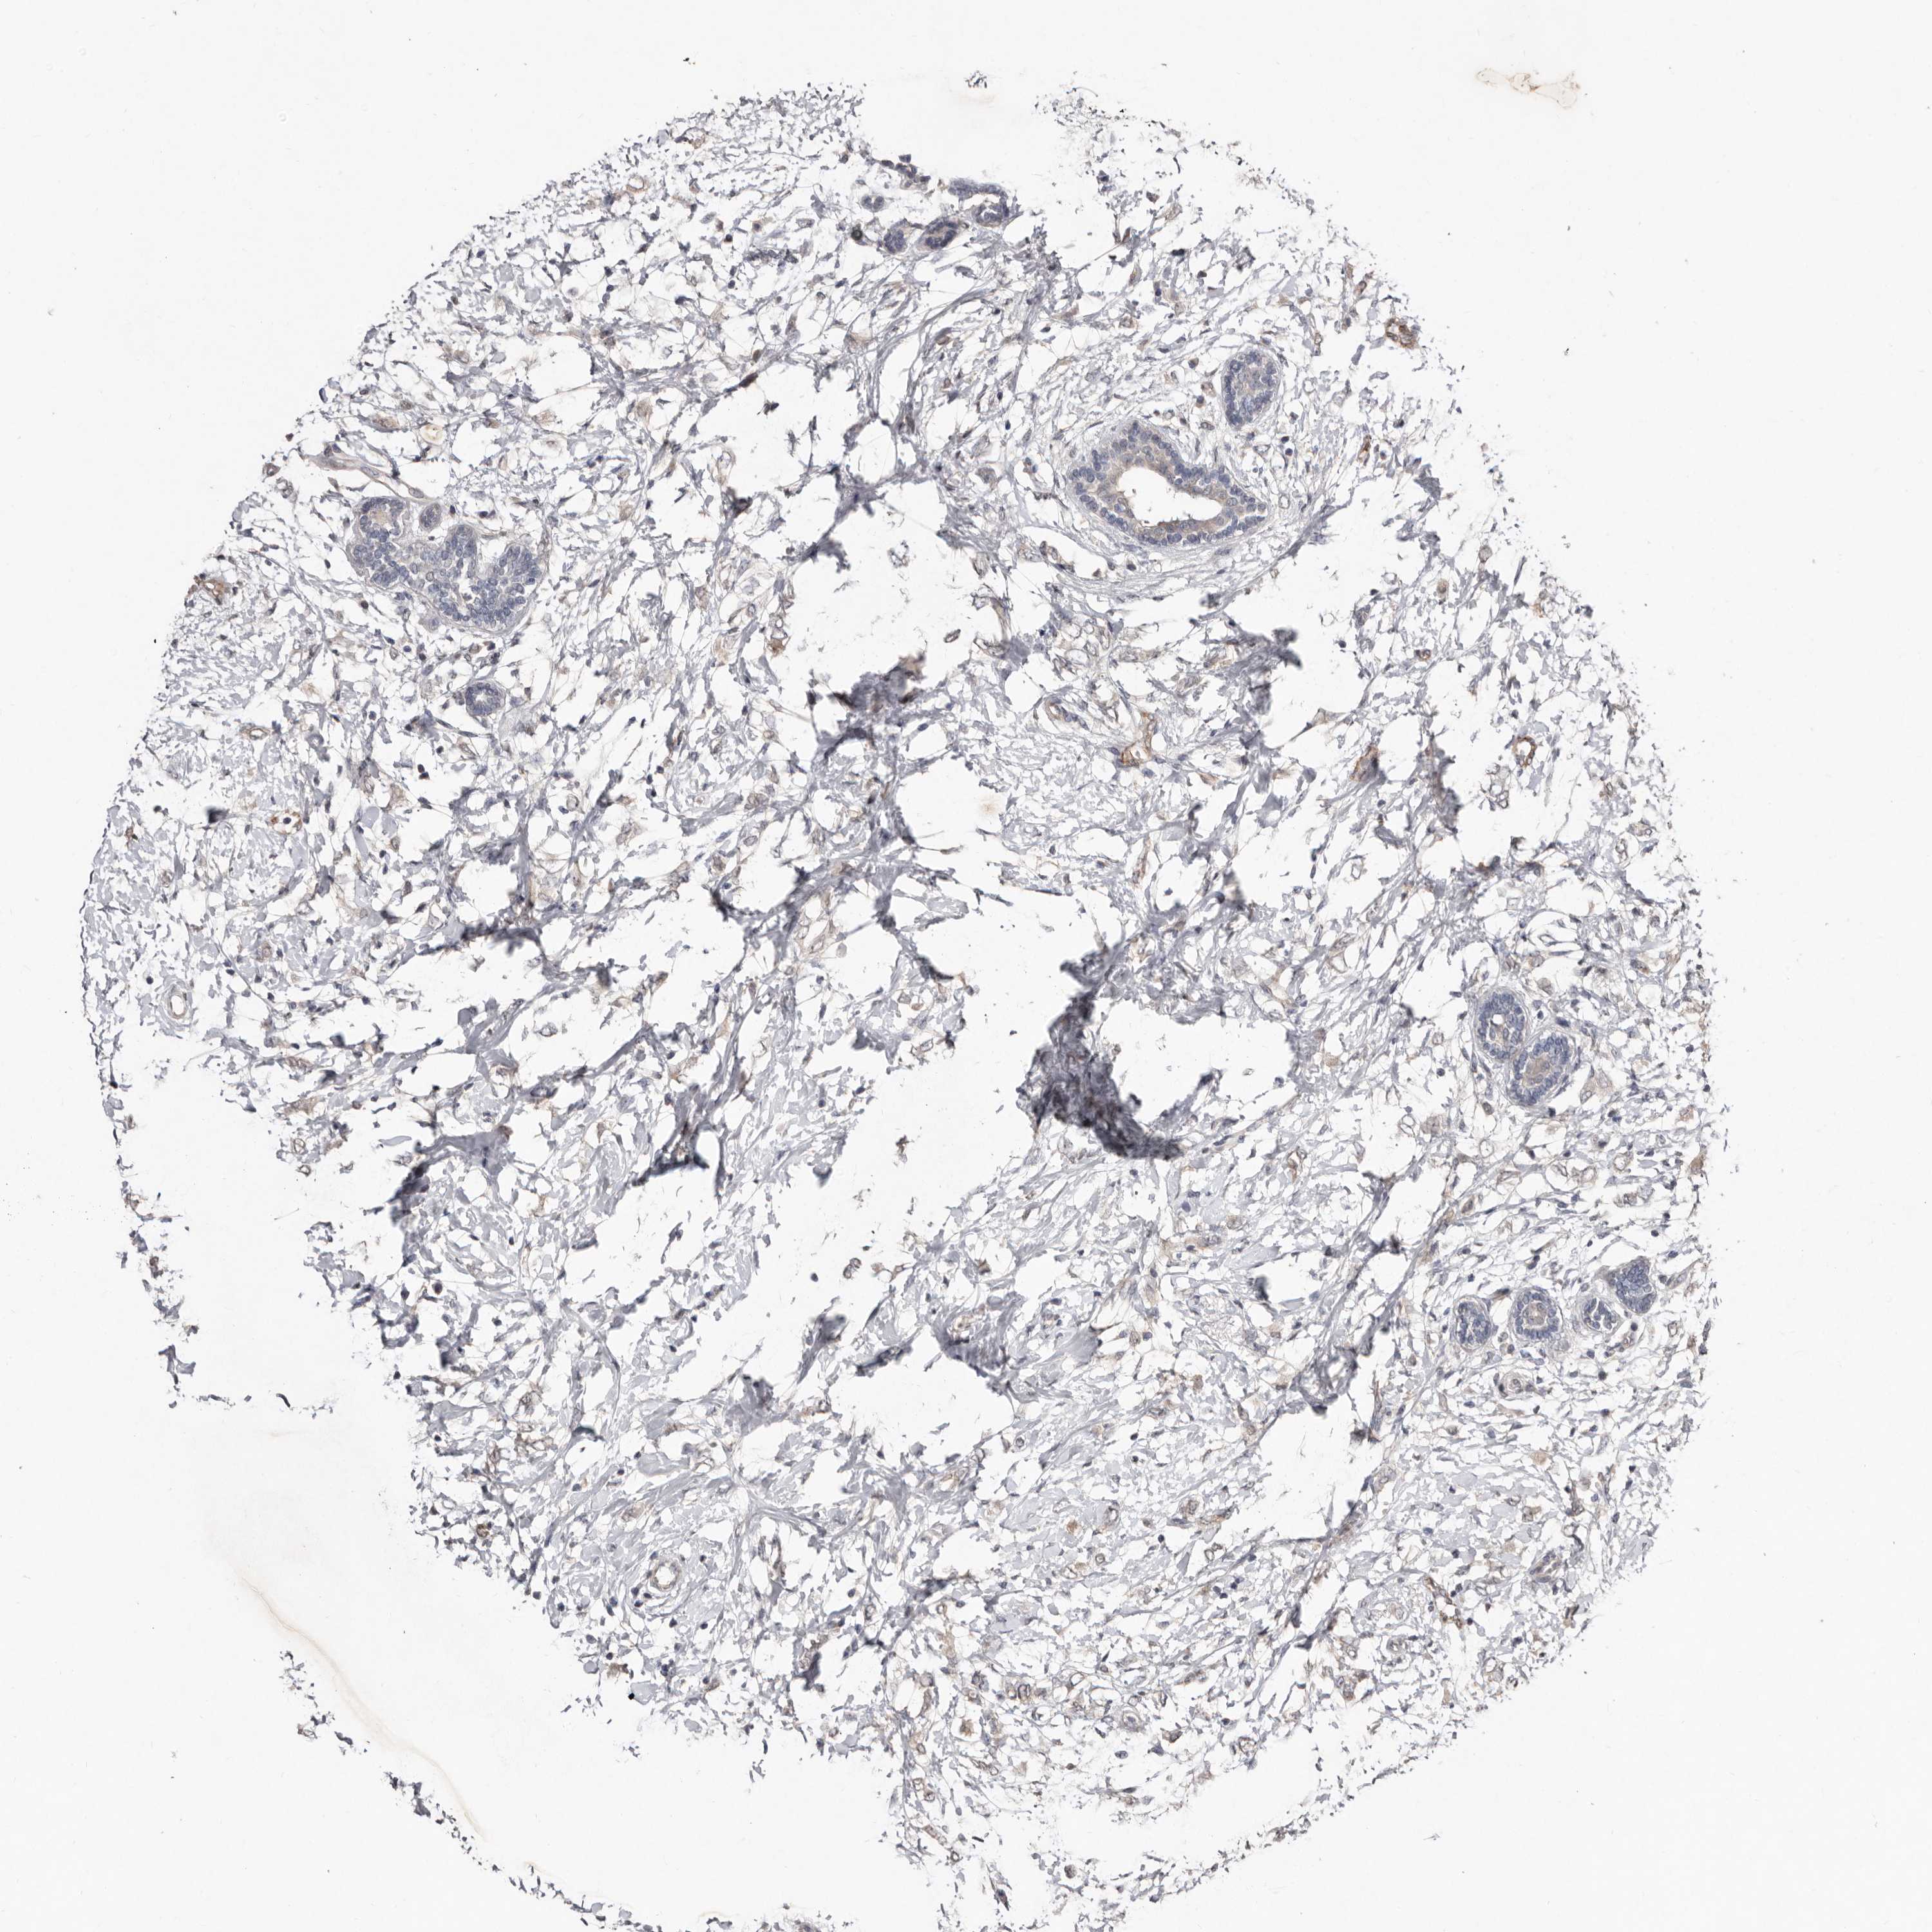

BRCA TCGA BRCA VALIDATION PROTEIN EXPRESSION